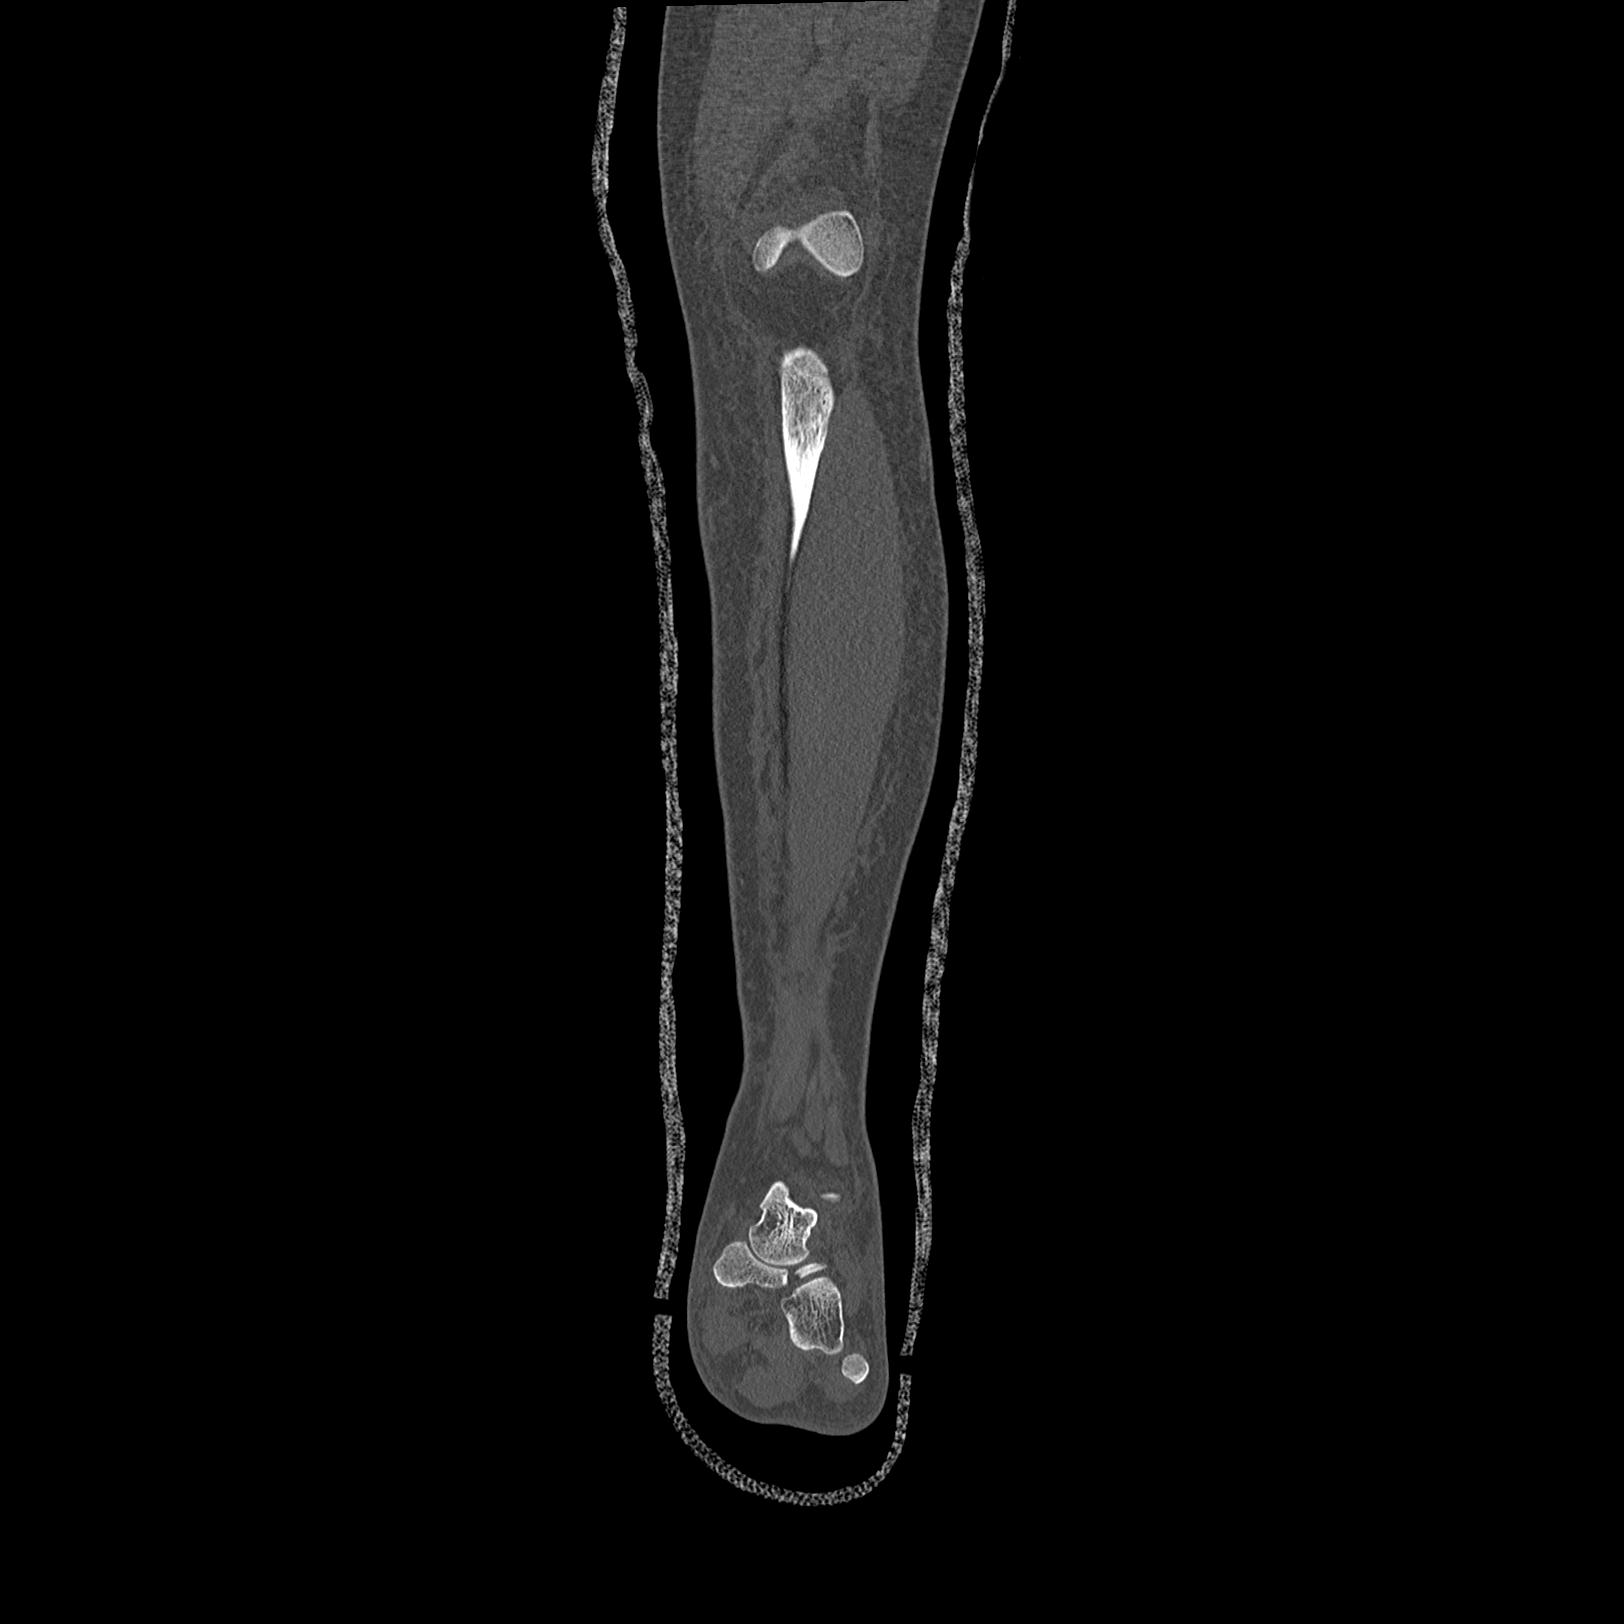

102803 1/12(キウスなし) 1/27 左下腿 4R 30歳女性 左脛骨軸内釘